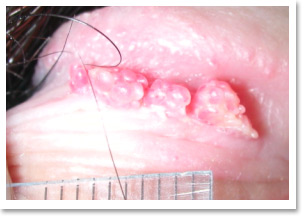

尖圭湿疣(condyloma acuminata菜花)是可以百分之百根治的病,只要假以